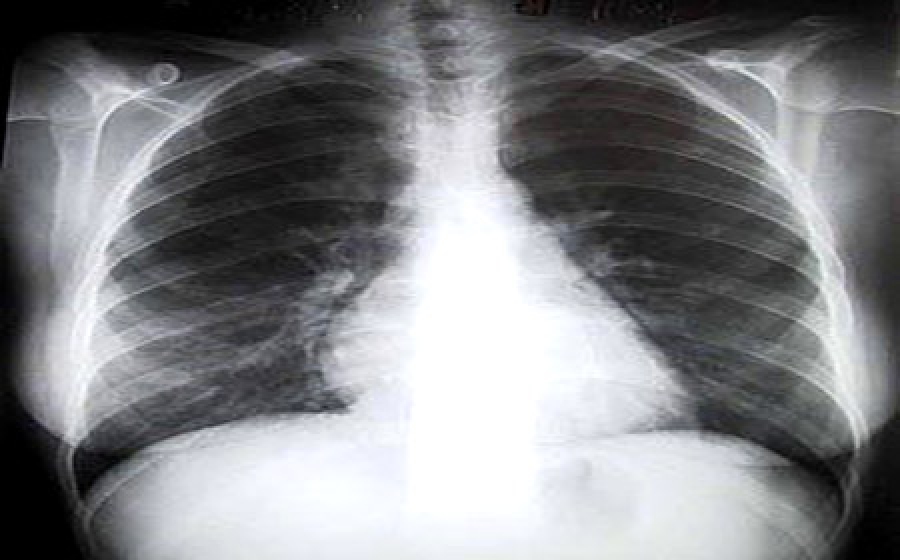

Dopo l’allarme per i possibili rischi per i militari in Afghanistan dovuti alla contaminazione con uranio impoverito ne arriva uno nuovo: chi torna da Iraq e Afghanistan potrebbe correre il rischio di sviluppare una malattia respiratoria rara nota come Brochiolite Costrittiva. A darne notizia oggi è il portale www.osservatoriomalattierare.it. “Uno studio condotto su 80 soldati americani rientrati dal Medio Oriente – si legge nell’articolo - ha evidenziato che più della metà dei militari presentava una dispnea da sforzo al rientro. La biopsia polmonare ha mostrato che quasi tutti i soldati rientrati dalle missioni con problemi respiratori sono affetti da bronchiolite costrittiva, probabilmente dipendente dall’inalazione di sostanze tossiche o dannose. Lo studio suggerisce quindi che esiste una stretta correlazione tra la bronchiolite costrittiva e la diminuzione delleprestazioni fisiche dei soldati che hanno prestato servizio in Medio Oriente” Lo studio in questione è stato condotto dal Medical Center della Vanderbilt Univeristy su un gruppo di 80 soldati provenienti da Fort Campell, in Kentuky, tra il febbraio 2004 e il dicembre 2006. Questi soldati, rientrati dall’Iraq o dall’Afghanistan, presentavano un’inspiegabile dispnea da sforzo (non erano in grado di portare a termine il normale esercizio fisico previsto dagli esercizi militari, due miglia di corsa). Molti di questi soldati sono stati esposti alle sostanze tossiche presenti nell’aria in seguito all’incendio della miniera sulfurea di Mosul (Iraq) durante l’estate 2003, ma non tutti. Di questi soldati 49 sono stati sottoposti a una biopsia polmonare toracoscopica, oltre ai controlli cardiopolmonari (spirometria e tutti gli altri controlli previsti dalle linee guida dell’American Thoracic Society). Per ben 38 dei soldati sottoposti a biopsia la diagnosi è stata di bronchiolite costrittiva. Inseguito gli stessi sono stati sottoposti a tomografia computerizzata elicale (CT) per ulteriori accertamenti. Quasi tutti i campioni delle biopsie hanno mostrato materiale polarizzabile corrispondente a inalazione di polveri sottili, nonostante la maggior parte dei soldati non sia mai stato fumatore. Le biopsie hanno anche mostrato ispessimenti delle pareti arteriolari o occlusioni di arterie adiacenti, solitamente causate da inalazioni di sostanze tossiche. L’età media del soldati che hanno preso parte a questo studio è di 33 anni, tutte persone in buono stato di salute, non affetti da patologie o sintomatologie respiratorie. Sarebbe stato semplice imputare la patologia all’esposizione inalatoria dell’incendio della miniera, ma solo 28 dei soldati esaminati ne sono stati interessati. Quasi tutti hanno riferito di aver respirato durante le tempeste di polvere (tipiche della zona) e di essere stati esposti all’incenerimento di rifiuti solidi in pozzi bruciati”.